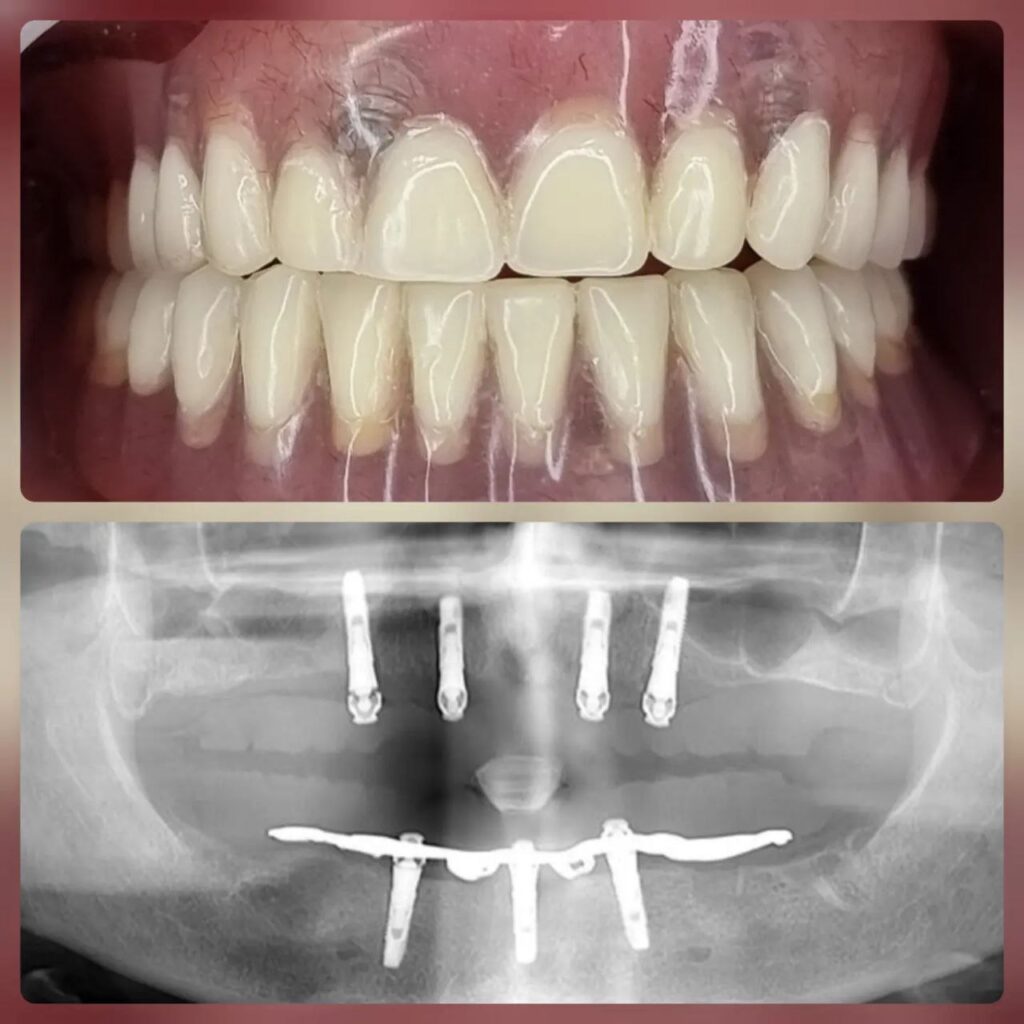

کاشت ایمپلنت دندان

اطمینان حاصل کردن از اینکه دندانهایتان به نحوی زیبا و طبیعی جایگزین شدهاند، از اهمیت بسیاری برخوردار است. ایمپلنت دندان به عنوان یک روش درمانی دائمی در دندانپزشکی شناخته میشود که حاصل آن، یک دندان زیبا و طبیعی در دهان شما خواهد بود.

هرچند که این روش درمانی هزینهی بیشتری نسبت به روشهای دیگر دارد، اما ارزش زیبایی که ایجاد میکند، قابل انکار نیست. ایمپلنتها به قدری شبیه به دندانهای طبیعی هستند که به سختی میتوان آنها را از دیگر دندانها تشخیص داد.